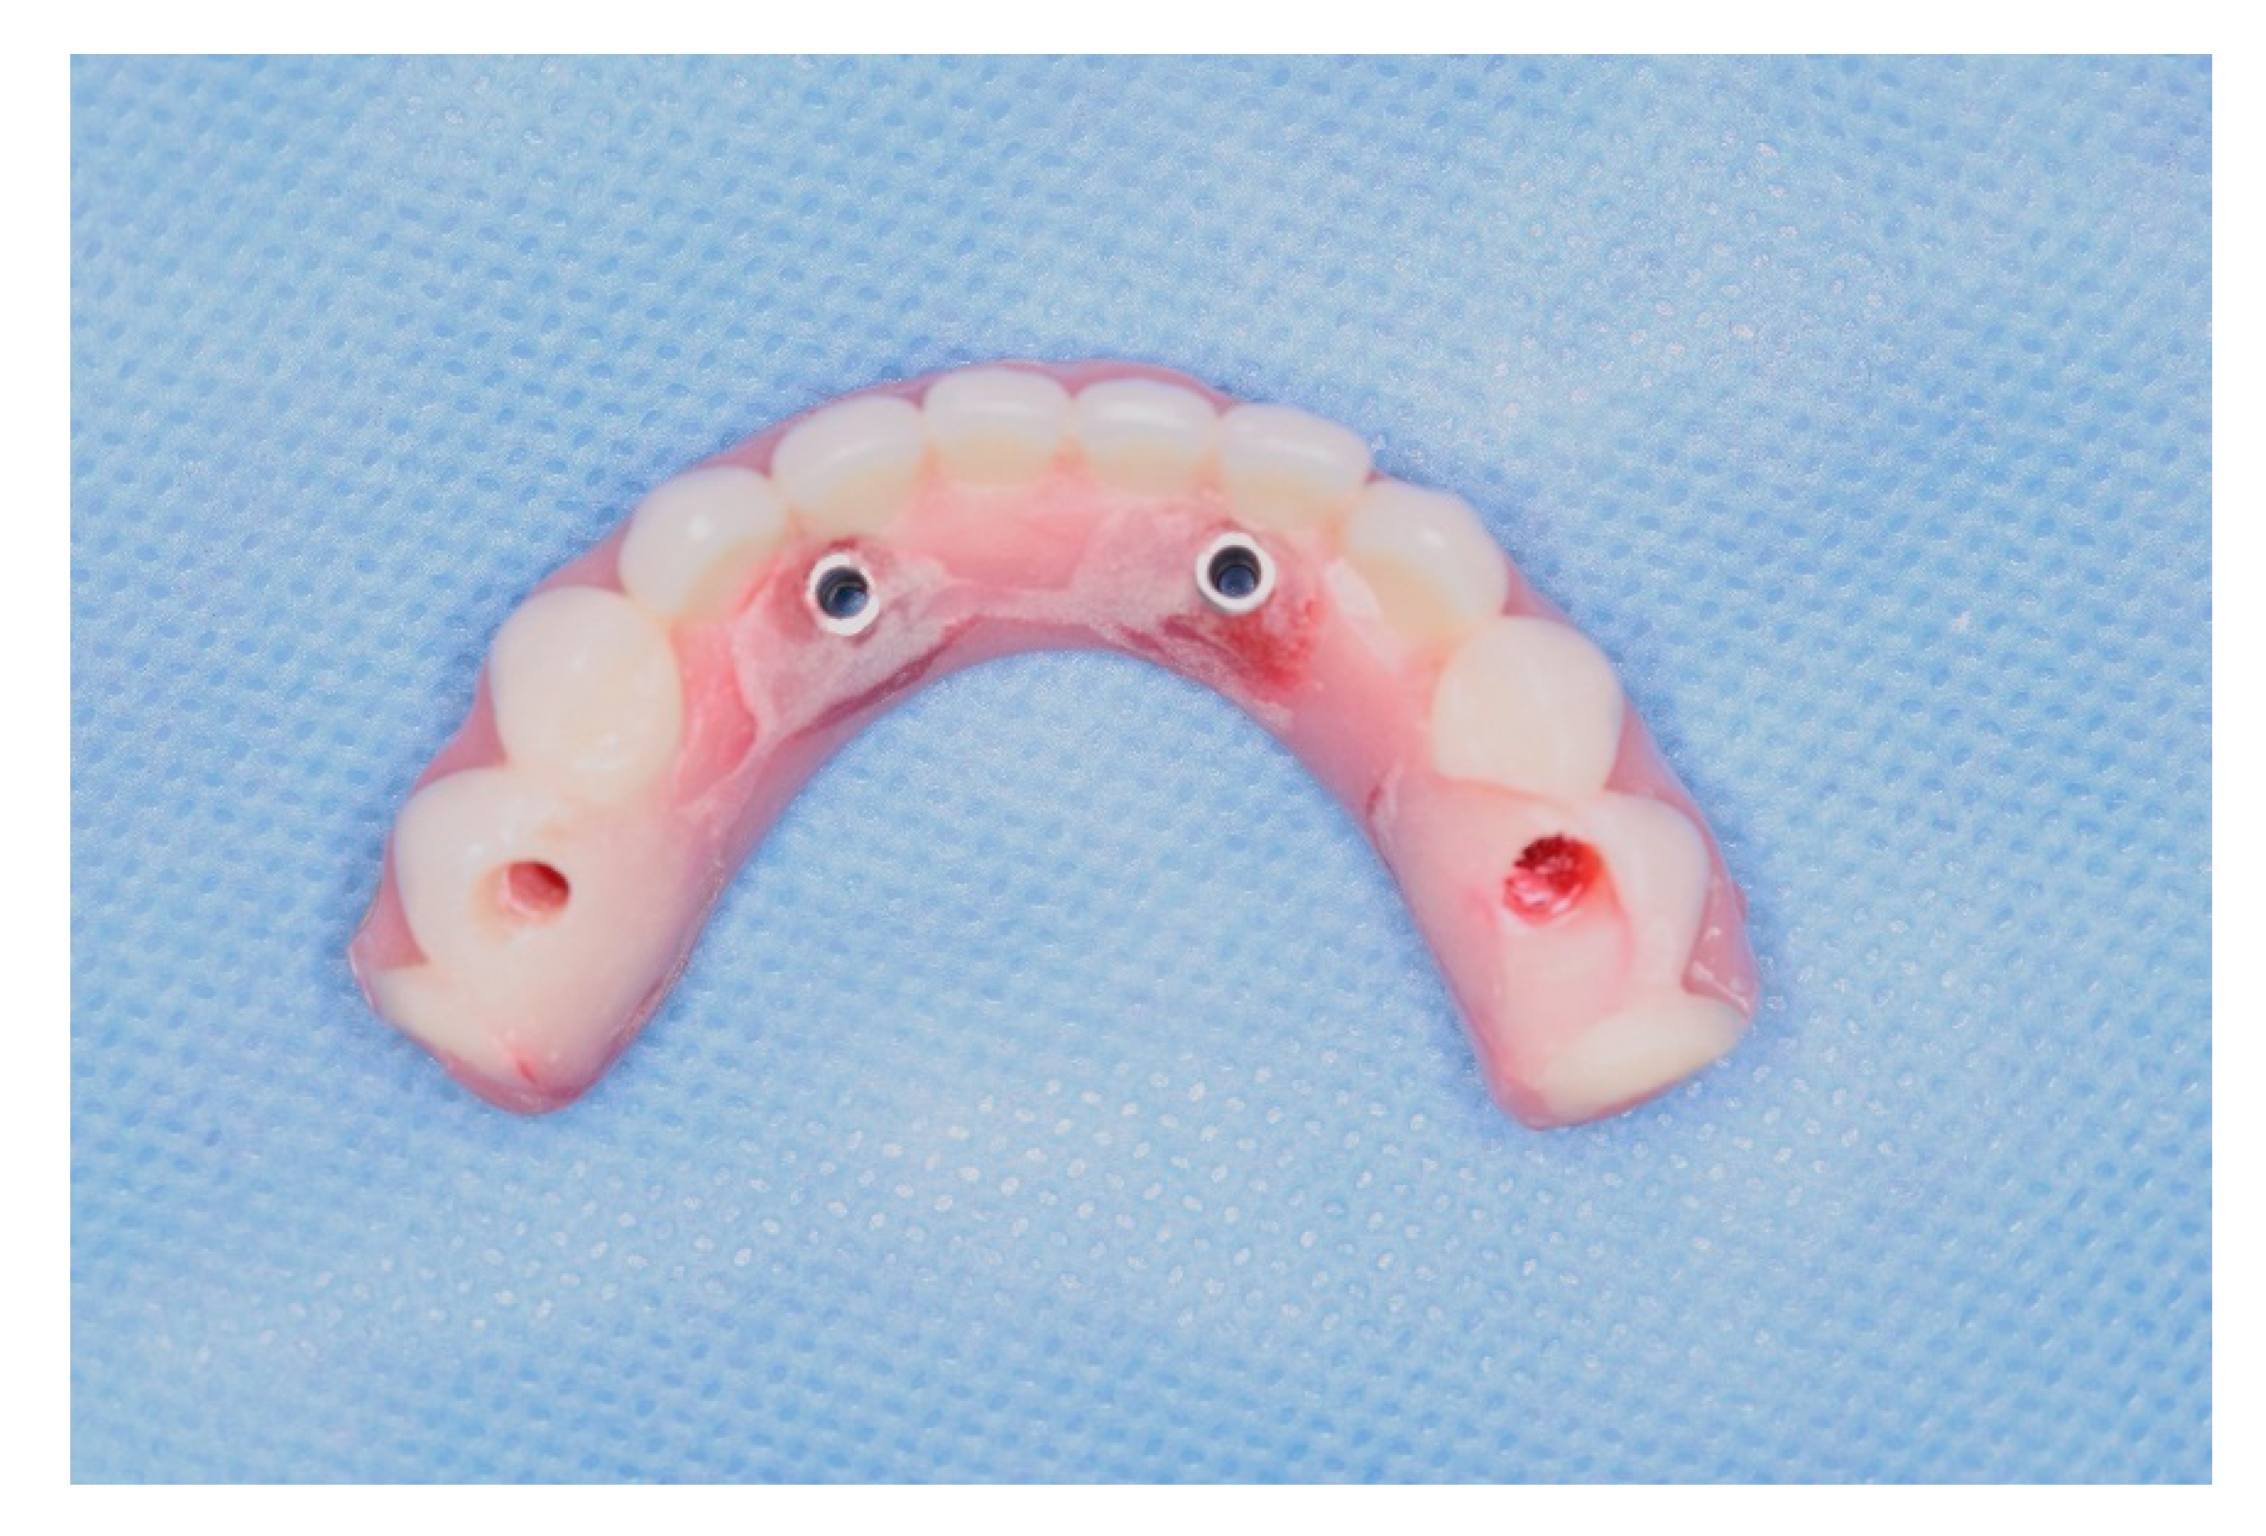

Figure 16. Inferior denture translated into a fixed screw-retained temporary full-arch prosthesis after modifications.

Pre-operatory medication consisted only on 2g of Amoxicillin one hour before the procedure, as suggested by her cardiologist. On surgery day, after anesthesia with Articaine 4% 1: 100,000 (DFL, Rio de Janeiro, Brazil), the computed surgical guide was placed in position, assured by the oclusal position on both sides and the stability over the patient’s mucosa, and in this position, fixed with the fixation pins after using their drills, assuring the guide immobilization (Figure 7). After that, we followed the guided bone instrumentation protocol recommended by the Plenum implant system (Plenum® Bioengenharia- Jundiaí, Brazil) to place 4 dental implants of 4.0x10mm with morse-tapper connection, produced by addtive manufacturing technology using titanium powder grade 23 (Figure 8), without raising a flap (Figure 9 and Figure 10). Because of this detail, very little bleeding was noted during the surgery. All implants were inserted with insertion torque ranging from 45 to 60 N/cm, assuring us the possibility for immediate load. The guide was removed (Figure 11) and four mini-conic abutments (Plenum® Bioengenharia- Jundiaí, Brazil), with 2mm high were installed on the implants. No suture was necessary and minimum trauma was noted on the soft tissue (Figure 12). Over these abutments, titanium cylinders were installed (Figure 13) and the lower denture was prepared to capture the implants position, translating the removable prosthesis into a fixed one (Figure 14 and Figure 15). Pattern Resin was used to unite the denture to the cylinders, and over the red resin, pink acrylic resin was used to improve the aesthetic appearance of the prosthesis. The denture was worn out in order not to touch the patient’s mucosa, and to diminish the cantilever we removed the molars from both sides of the denture (Figure 16) and installed the temporary fixed screw retained full-arch rehabilitation (Figure 17 and Figure 18). With this, the patient left the surgical appointment with an immediate load implant rehabilitation. Post operatory medication consisted on 600mg of Ibuprofen, twice a day during 3 days, if necessary. She was instructed to put ice bags on the surgical area during 48 hours, about 15 minutes every hour. On the day before surgery the patient suspended the medication because she had no pain. The patient was also instructed not to sleep with the opposing complete denture for 7 days and feed only with soft foods.

After a healing period of 3 months the patient returned to change que temporary fixed prothesis for a new one, more delicate and with a reinforced metallic bar for a better ferulization of the implants and better dissipation of the stress during function. After removal of the temporary prosthesis we could see the peri-implant mucosa was healthy (Figure 19), without bleeding on probe nor peri-implant sulcus with more than 3mm depth, even around the implants were there were lack of a satisfactory keratinized tissue band, showing us that the patient was being able to maintain the cleansing of the region below the prosthesis. A new fixed rehabilitation over the implants was produced (Figure 20, Figure 21 and Figure 22). 2 years after the surgery we could see on a control panoramic radiograph no signs of bone remodeling above the expected around the implants (Figure 23).